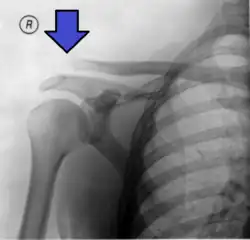

An Xray showing a separated shoulder. Notice the separation between the end of the collarbone and the scapula. | |

X-ray indicates a separated shoulder when the acromioclavicular joint space is widened (it is normally 5 to 8 mm).[9]